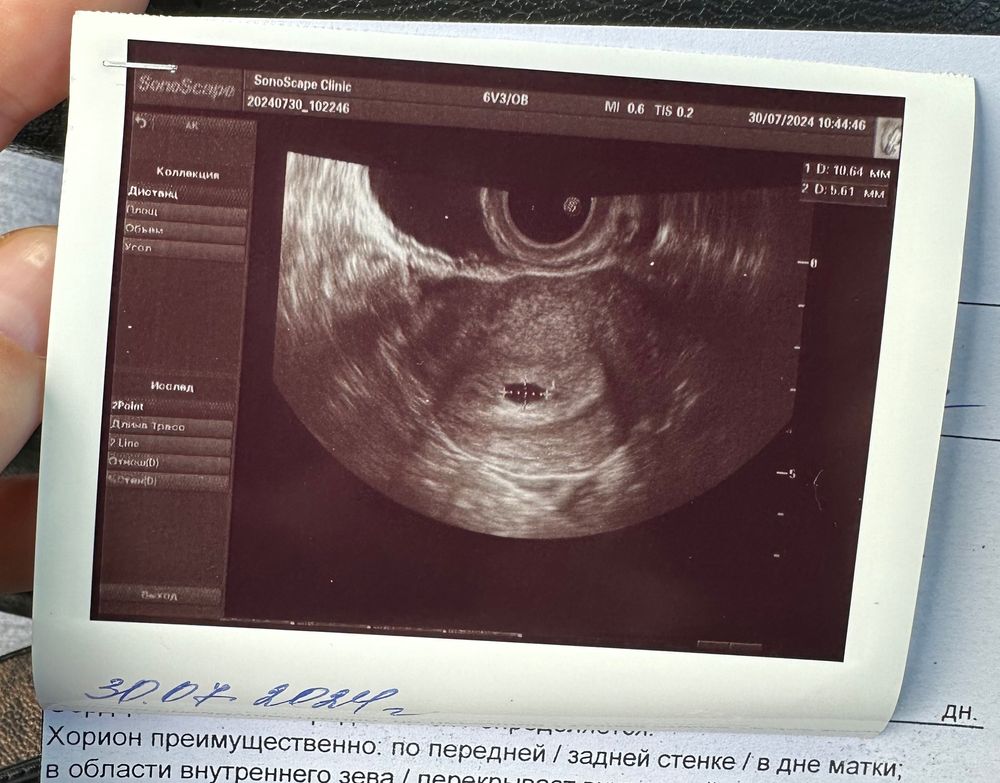

УЗИ 21 дпп

Результаты УЗИДевочки, была сегодня на узи 21 дпп, посмотрели очень быстро, только сам факт наличия пя в матке, а я растерялась, не спросила про жм, теперь переживаю😕 УЗИ в доступности сейчас только такое, за более качественным аппаратом нужно ехать.

Это нормально что пя вытянутое? 10,6 на 5,6.

Мне кажется в правом углу что-то есть или кажется, все фото с замерами. У меня была точно такая же форма на 18дпп, ничего страшного. Про жм тоже сказали что нет, но мне кажется на фото в нижнем углу он был. Рано еще переживать, у вас хгч пониже.

Ирина, слушайте, точно, под цифрой 1 на моих снимках как будто что то есть🙏🏻 фото без замеров нет к сожалению. Спасибо 🙏🏻🙏🏻🙏🏻 А дальше у вас какие результаты узи?